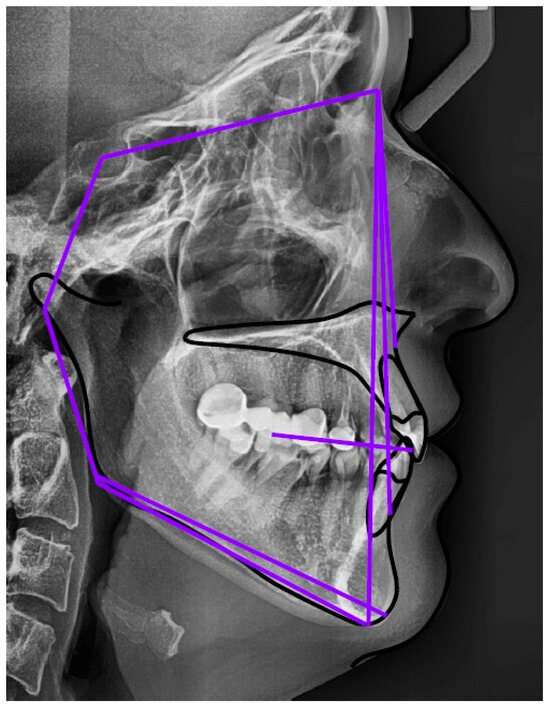

2.1. Distribution into Skeletal Classes